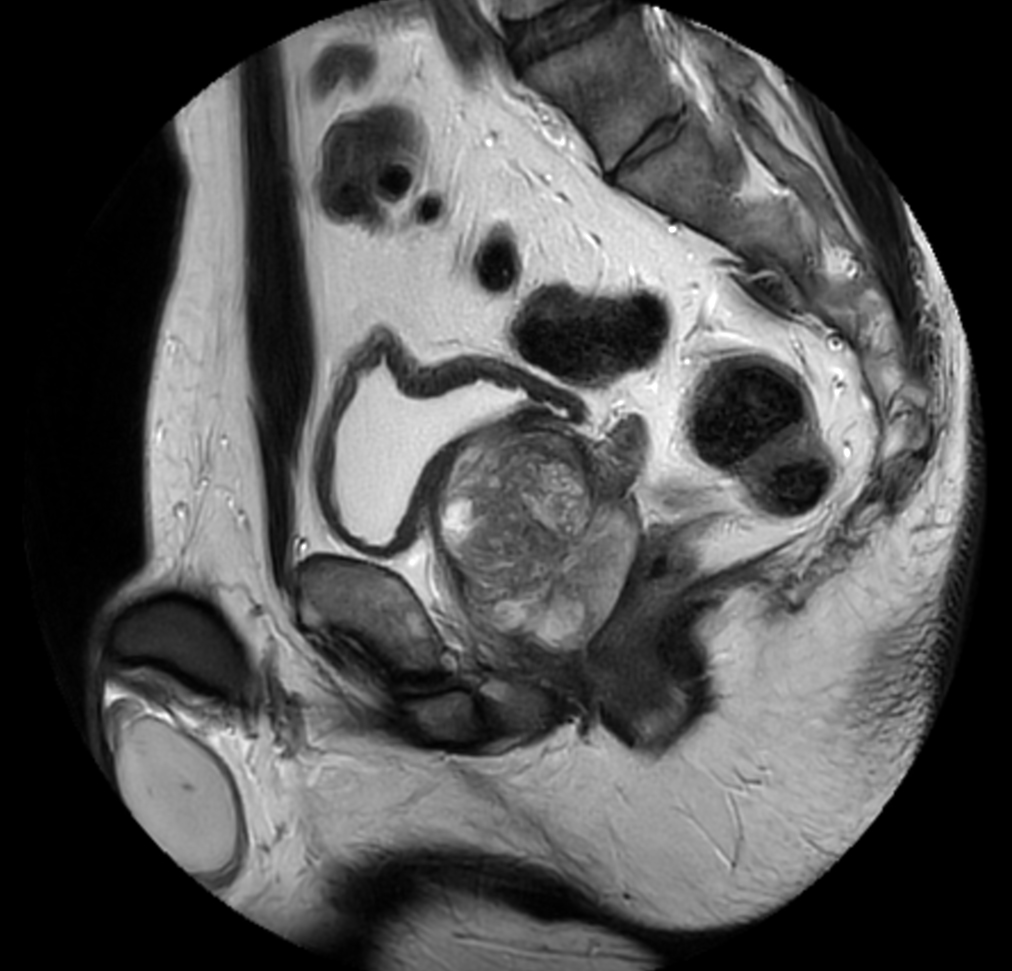

Sagittal T2w TSE - MultiVane XD